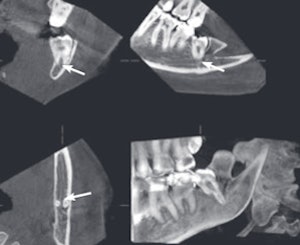

An example of cone-beam CT. In this instance, the lower left third molar (d. 38) was imaged after panoramic radiograph with CBCT. The arrows mark the mandibular canal. Images courtesy of Dr. Anni Suomalainen.